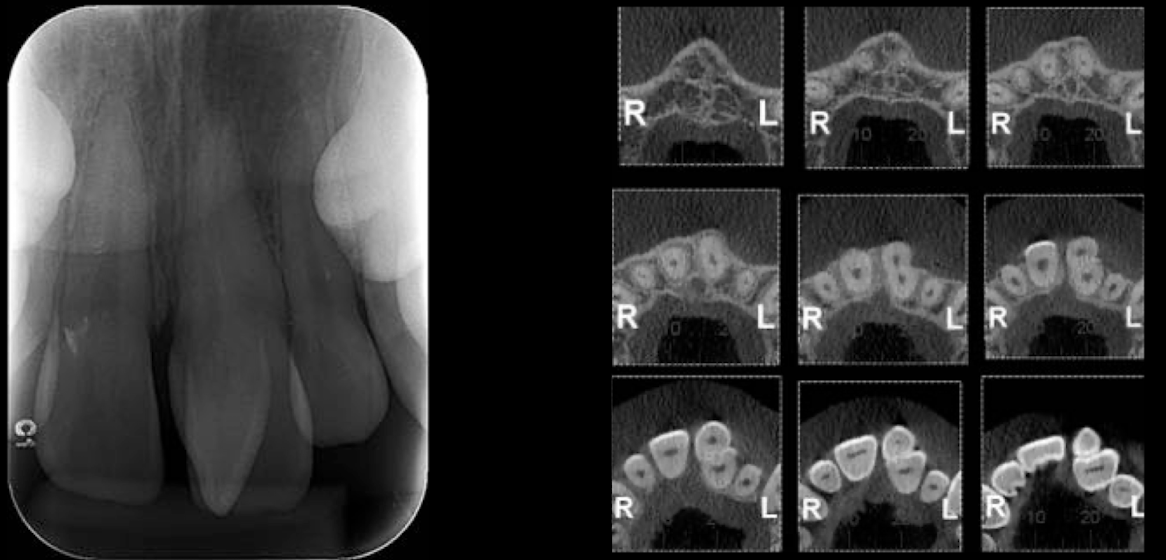

Based on this xray, what developmental and congenital abnormality is observed?

a. number of teeth

b. size of teeth

c. eruption of teeth

d. morphology of teeth